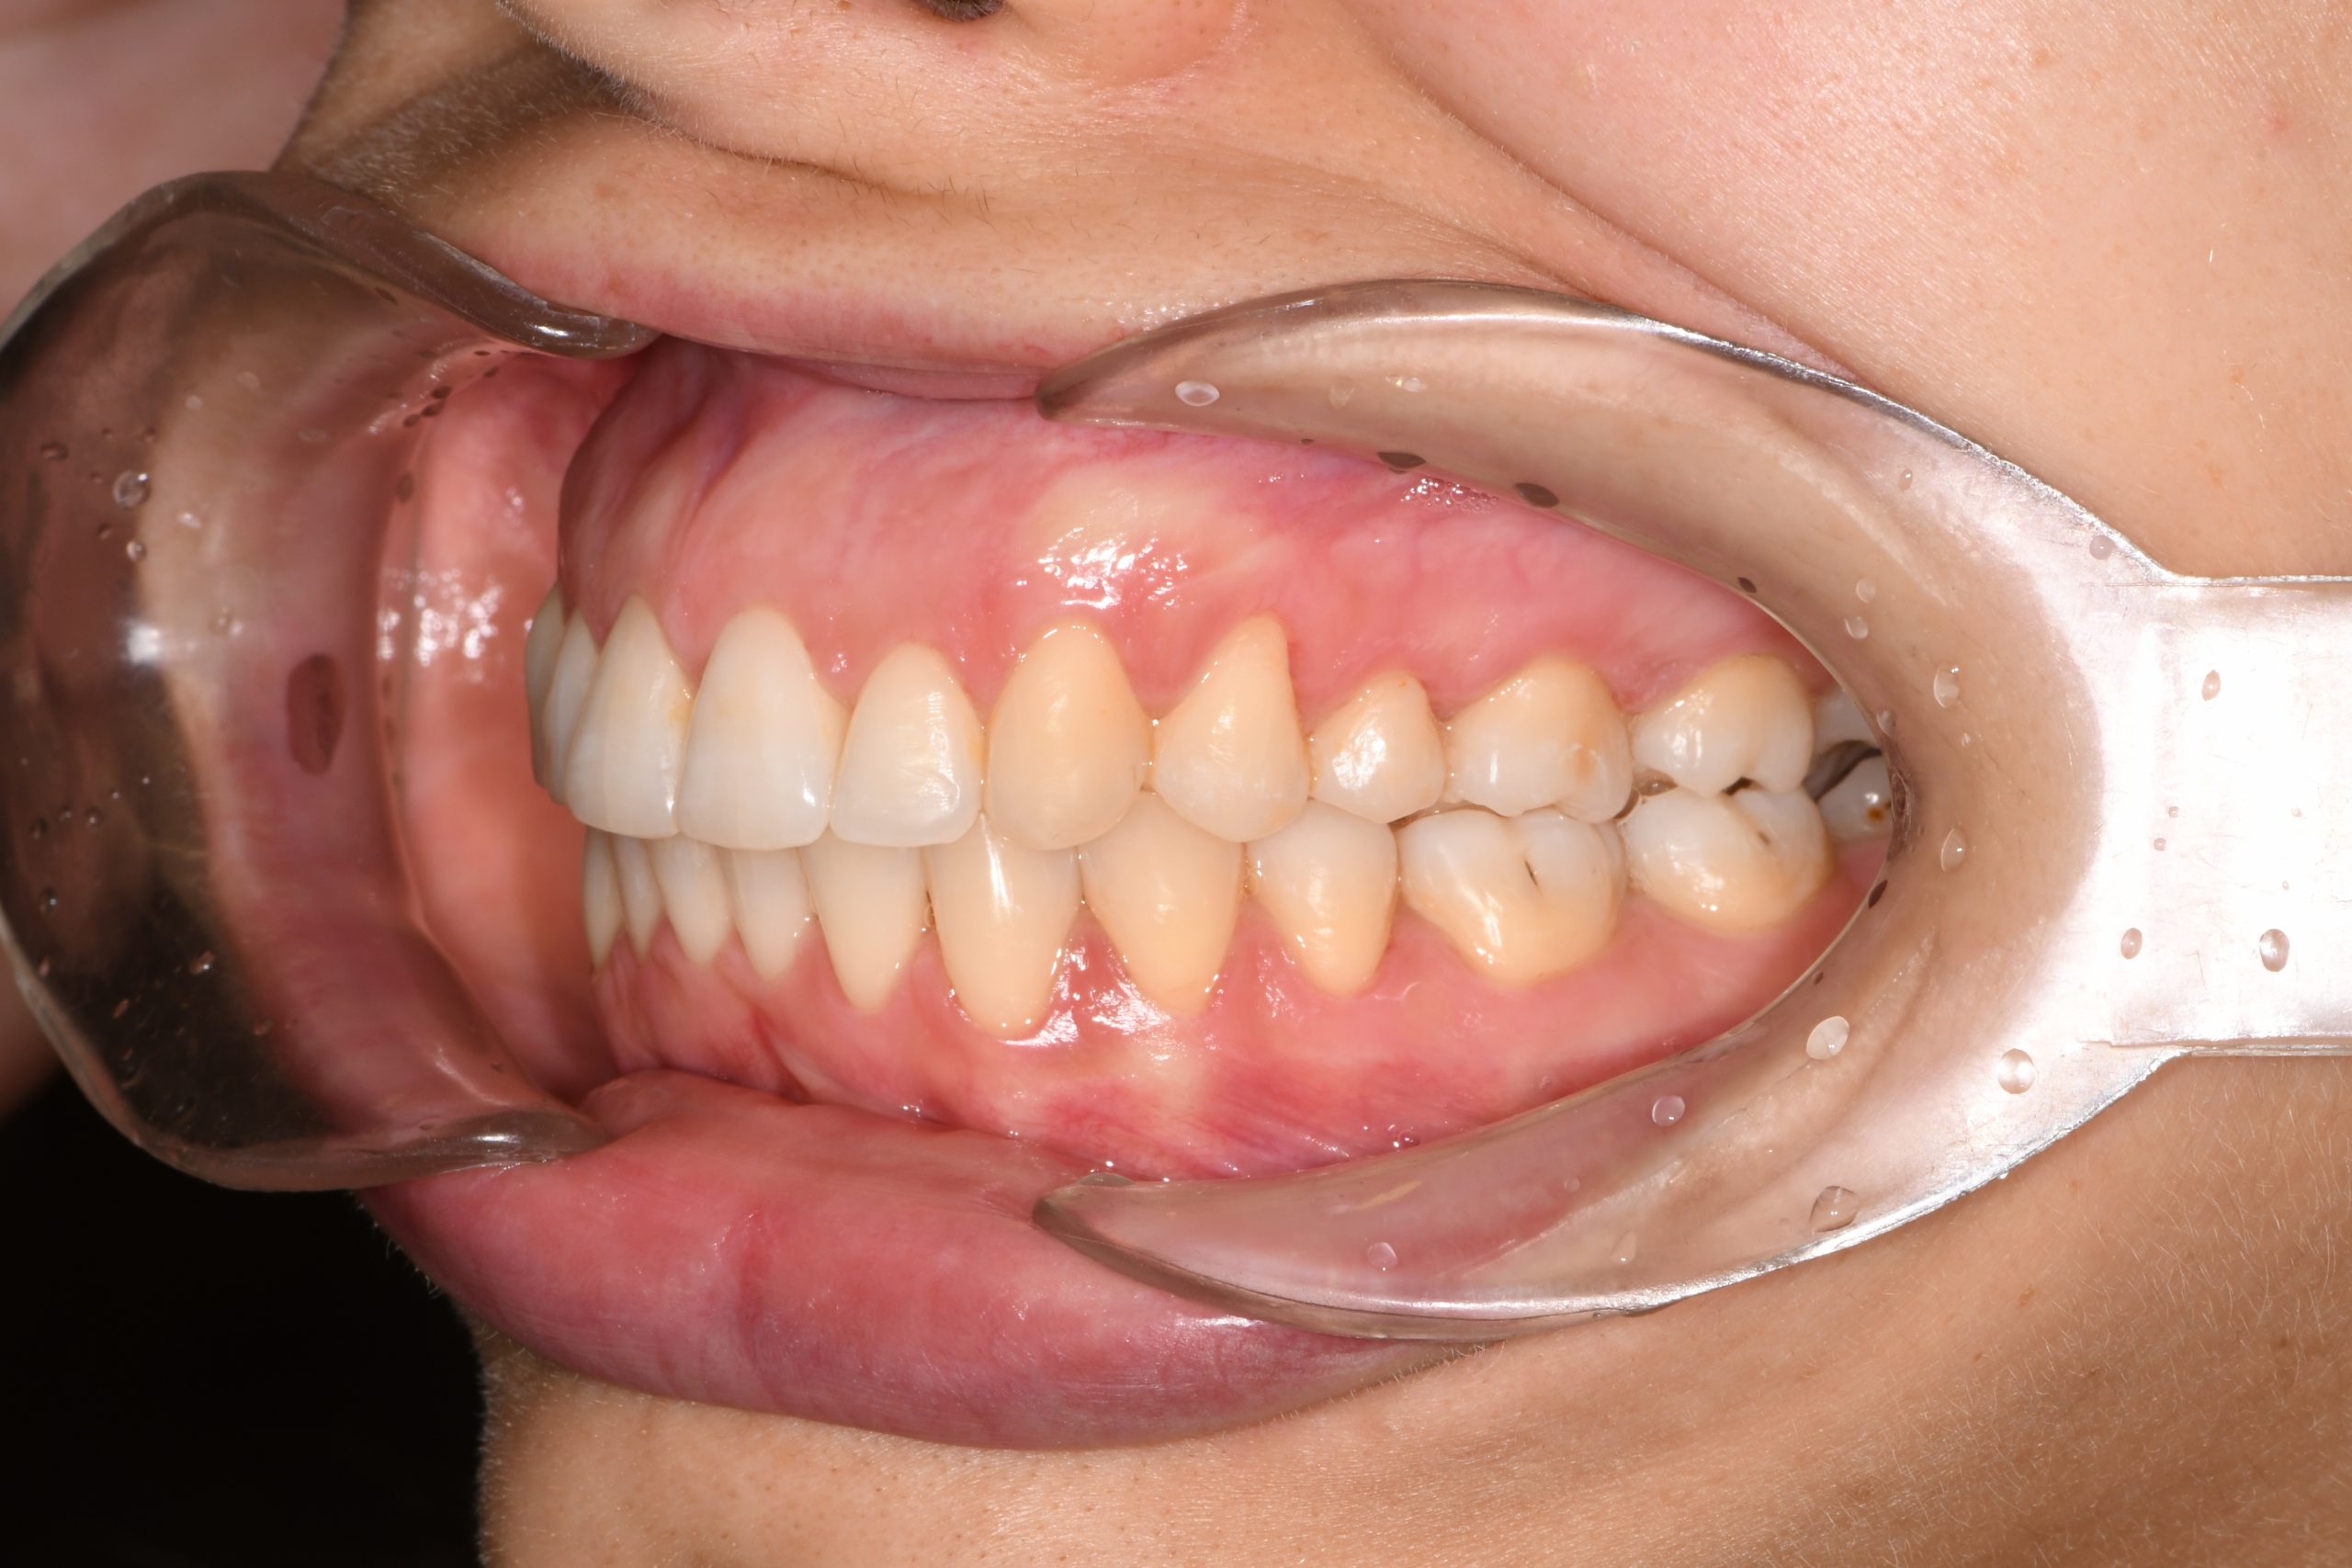

Az elmúlt évekből rengeteg szakmai referenciát tudnánk bemutatni, amelyek különböző fogszabályozási problémákat oldottak meg. Válogatva a több száz esetből, ezen az oldalon olyan képeket, információkat igyekeztünk bemutatni, amelyeknek a segítségével a jövőbeni pácienseinknek azt tudjuk üzenni: A Te fogsorod is lehet gyönyörű!

(Képeket a Pácienseink külön írásos beleegyezésével mutatjuk be!)